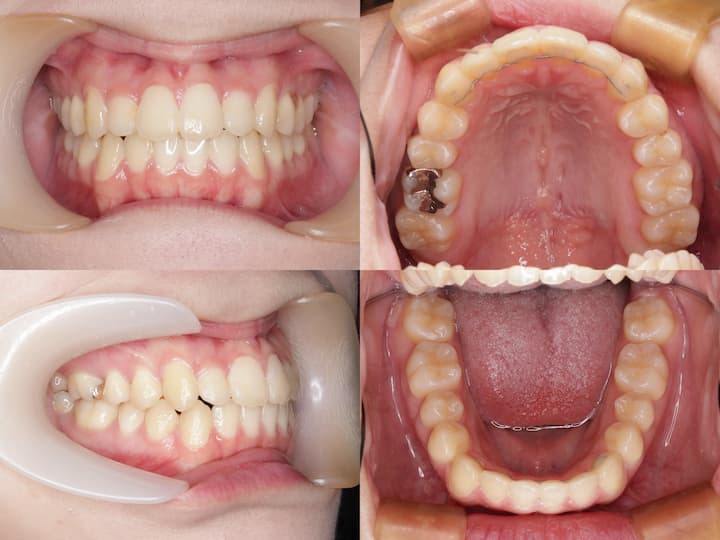

ハーフリンガル矯正装置を採用し、上顎は舌側矯正装置(リンガルブラケット)、下顎は唇側矯正装置(ラビアルブラケット)を使用しました。上顎大臼歯の圧下とアンカレッジコントロール

本症例の治療成功の鍵は、上顎大臼歯の確実な圧下とAngleⅠ級臼歯関係の維持にあります。以下の治療メカニクスを採用しました。

・i-station(歯科矯正用アンカースクリュー)の植立:正中口蓋縫合部に植立し、上顎大臼歯の固定源として使用

・上顎大臼歯の圧下:i-stationからの圧下力により、上顎大臼歯を垂直的に圧下

・上顎大臼歯の固定:抜歯スペース閉鎖時の近心移動を防止し、AngleⅠ級臼歯関係を維持